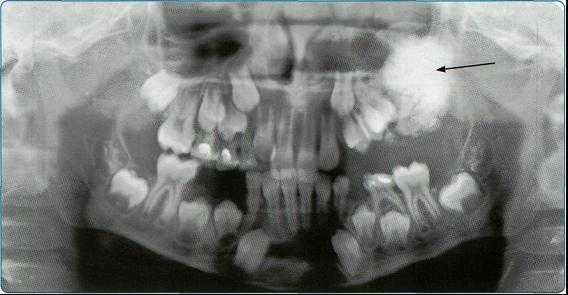

5. Ортопантомография

Панорамная зонография, или, как ее чаще называют, ортопантомография, явилась своего рода революцией в рентгенологии челюстно-лицевой области и не имеет себе равных по ряду показателей (обзор большого отдела лицевого черепа в идентичных условиях, минимальная лучевая нагрузка, малые затраты времени на исследование).

Панорамная зонография позволяет получить плоское изображение изогнутых поверхностей объемных областей, для чего используют вращение рентгеновской трубки и кассеты.

Преимуществом ортопантомографии является возможность демонстрировать межчелюстные контакты, оценивать Результаты воздействия межчелюстной нагрузки по состоянию замыкающих пластинок лунок и определять ширину периодонтальных путей.

Ортопантомограммы демонстрируют взаимоотношения зубов верхнего ряда с дном верхнечелюстных пазух и позволяют выявить в нижних отделах пазух патологические изменения одонтогенного генеза.

Особенно важно использовать ортопантомографию в детской стоматологии, где она не имеет конкурентов в связи с низкими дозами облучения и большим объемом получаемой информации. В детской практике ортопантомография помогает диагностировать переломы, опухоли, остеомиелит, кариес, периодонтиты, кисты, определять особенности прорезывания зубов и положение зачатков.